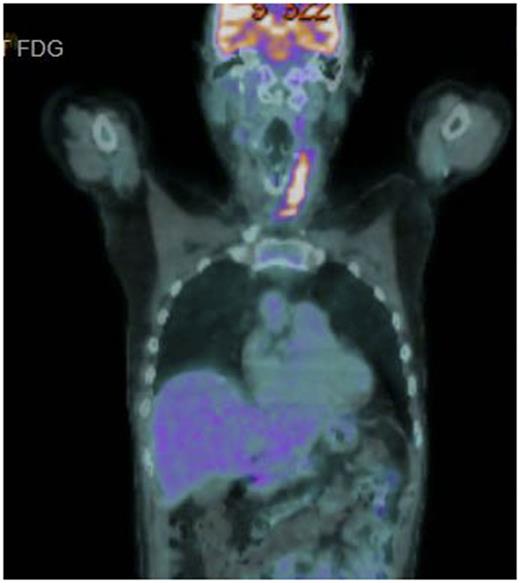

A 56 year old male presented with rapid onset superior vena cava obstruction that caused an intensive care admission at the time of diagnosis. Staging showed stage 2 with neck disease, near complete SVC obstruction and a 6 x 5 x 5cm superior mediastinal mass. Therapy was commenced with R CODOX-M / R IVAC with an initial symptomatic improvement but by the time of recovery from course 2, the symptoms of respiratory distress were recurring in the left neck where partial acute respiratory obstruction occurred. No significant improvement in the neck mass was seen on repeat CT and urgent radiotherapy (R/T) was given to relieve symptoms. Persistent active disease was then confirmed by CT /PET scanning in the left neck (SUV 10.8), an exemplar image of this scan is shown in Figure. The patient was counselled as to the dire prognosis but was unwilling to accept that further intensive treatment was unlikely be successful and requested further chemotherapy. In the light the intensity of the treatment already delivered a novel strategy was conceived and agreed.